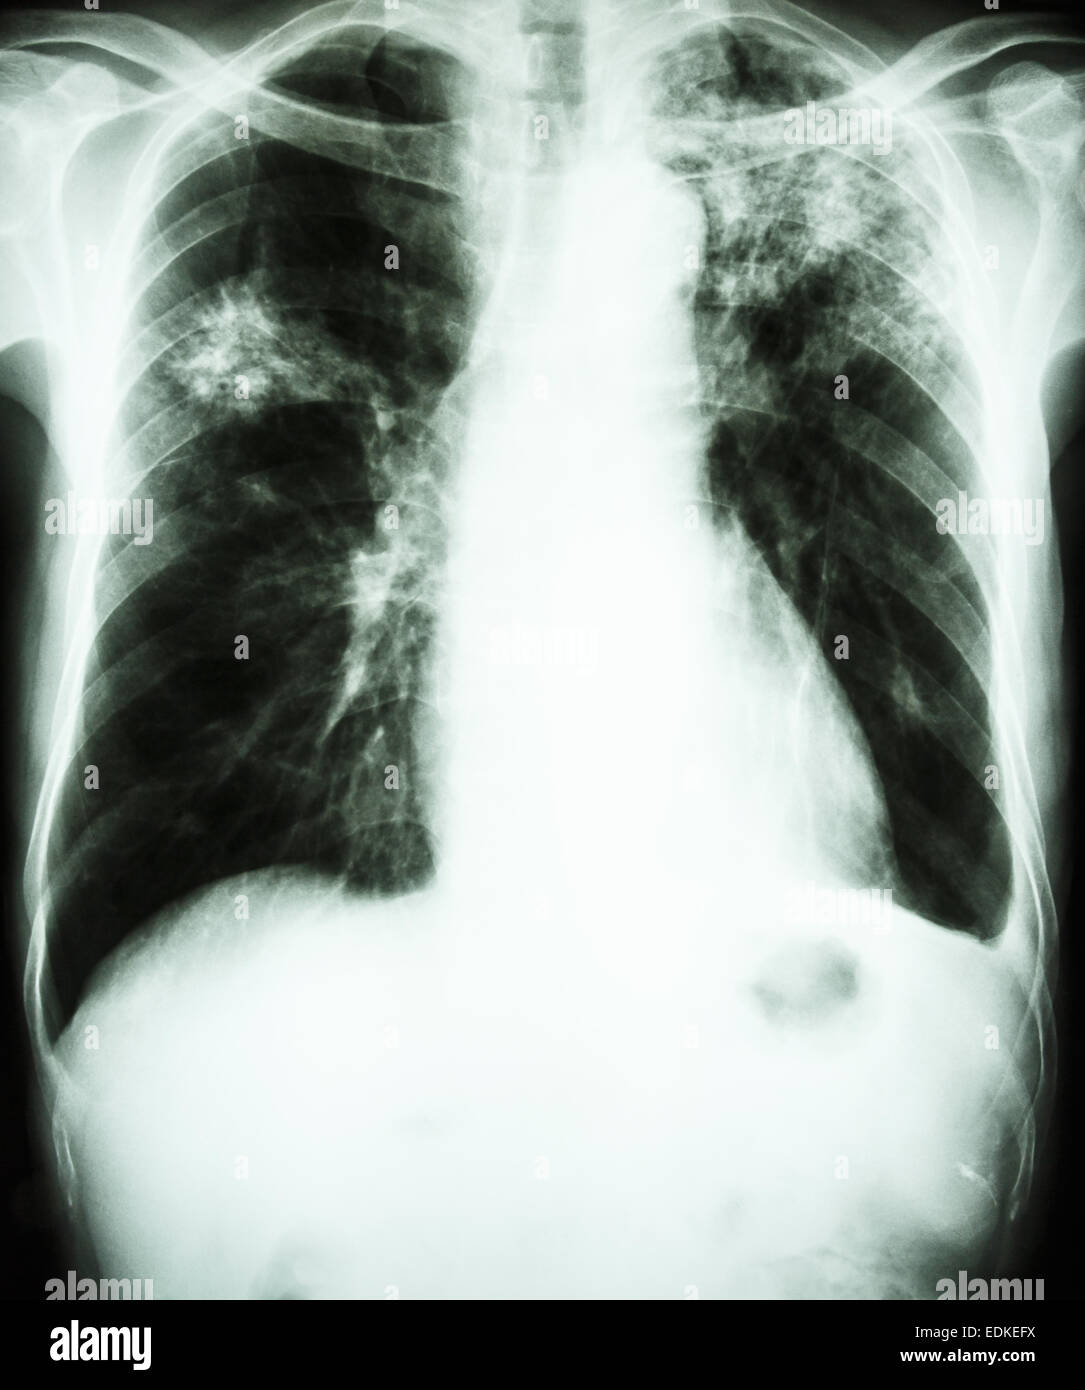

Снимок легких при туберкулезе является важным методом диагностики этого заболевания. На рентгеновских снимках можно увидеть изменения в легких, которые свойственны туберкулезу.

Очаговый туберкулез рентген

Рентген грудной клетки туберкулез

Фотографии снимков легких при туберкулезе

В данной статье представлены многочисленные фотографии снимков легких при туберкулезе, чтобы помочь вам понять, как выглядят изменения легких на рентгеновских снимках при этом заболевании.